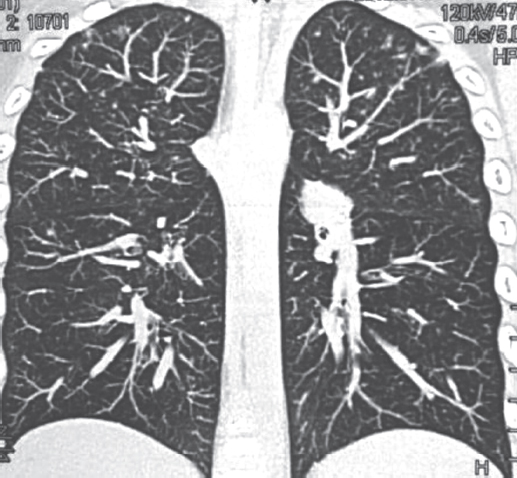

Анамнез заболевания. В процессе диспансерного наблюдения по туберкулезному контакту, в связи с положительной пробой с аллергеном туберкулезным рекомбинантным, проведена впервые мультиспиральная компьютерная томография (МСКТ) органов грудной полости 22.08.2011 (рис. 1) с внутривенным контрастированием. Заключение: «В легких без очаговых и инфильтративных изменений. Выявляются лимфоузлы трахеобронхиальной группы справа (до 8 мм), трахеобронхиальной группы слева (до 7 мм), лимфатические узлы корней легких с двух сторон (до 6 мм), бифуркационной группы (до 7 мм). В структуре лимфатических узлов корней легких и вдоль промежуточного бронха множественные кальцинаты».

Рис. 1. Пациент, 5 лет. Компьютерная томография грудной клетки (туберкулез внутригрудных лимфоузлов) от 22.08.2011

Fig. 1. Patient, 5 years old. Computed tomography of the chest (tuberculosis of the intrathoracic lymph nodes), 22.08.2011